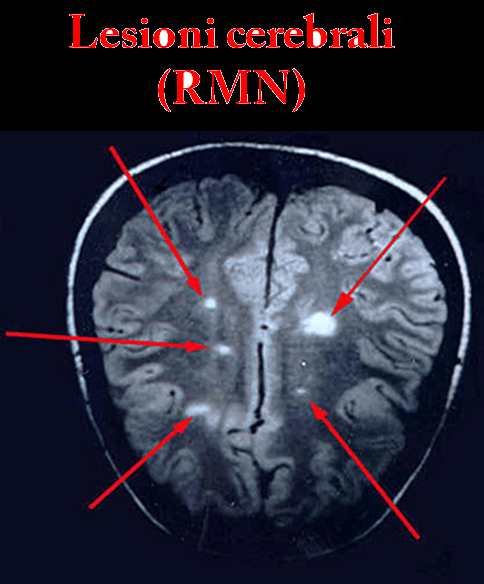

Risonanza Magnetica E Ictus Diagnostica Precoce Nell Infarto Cerebrale Nurse Times